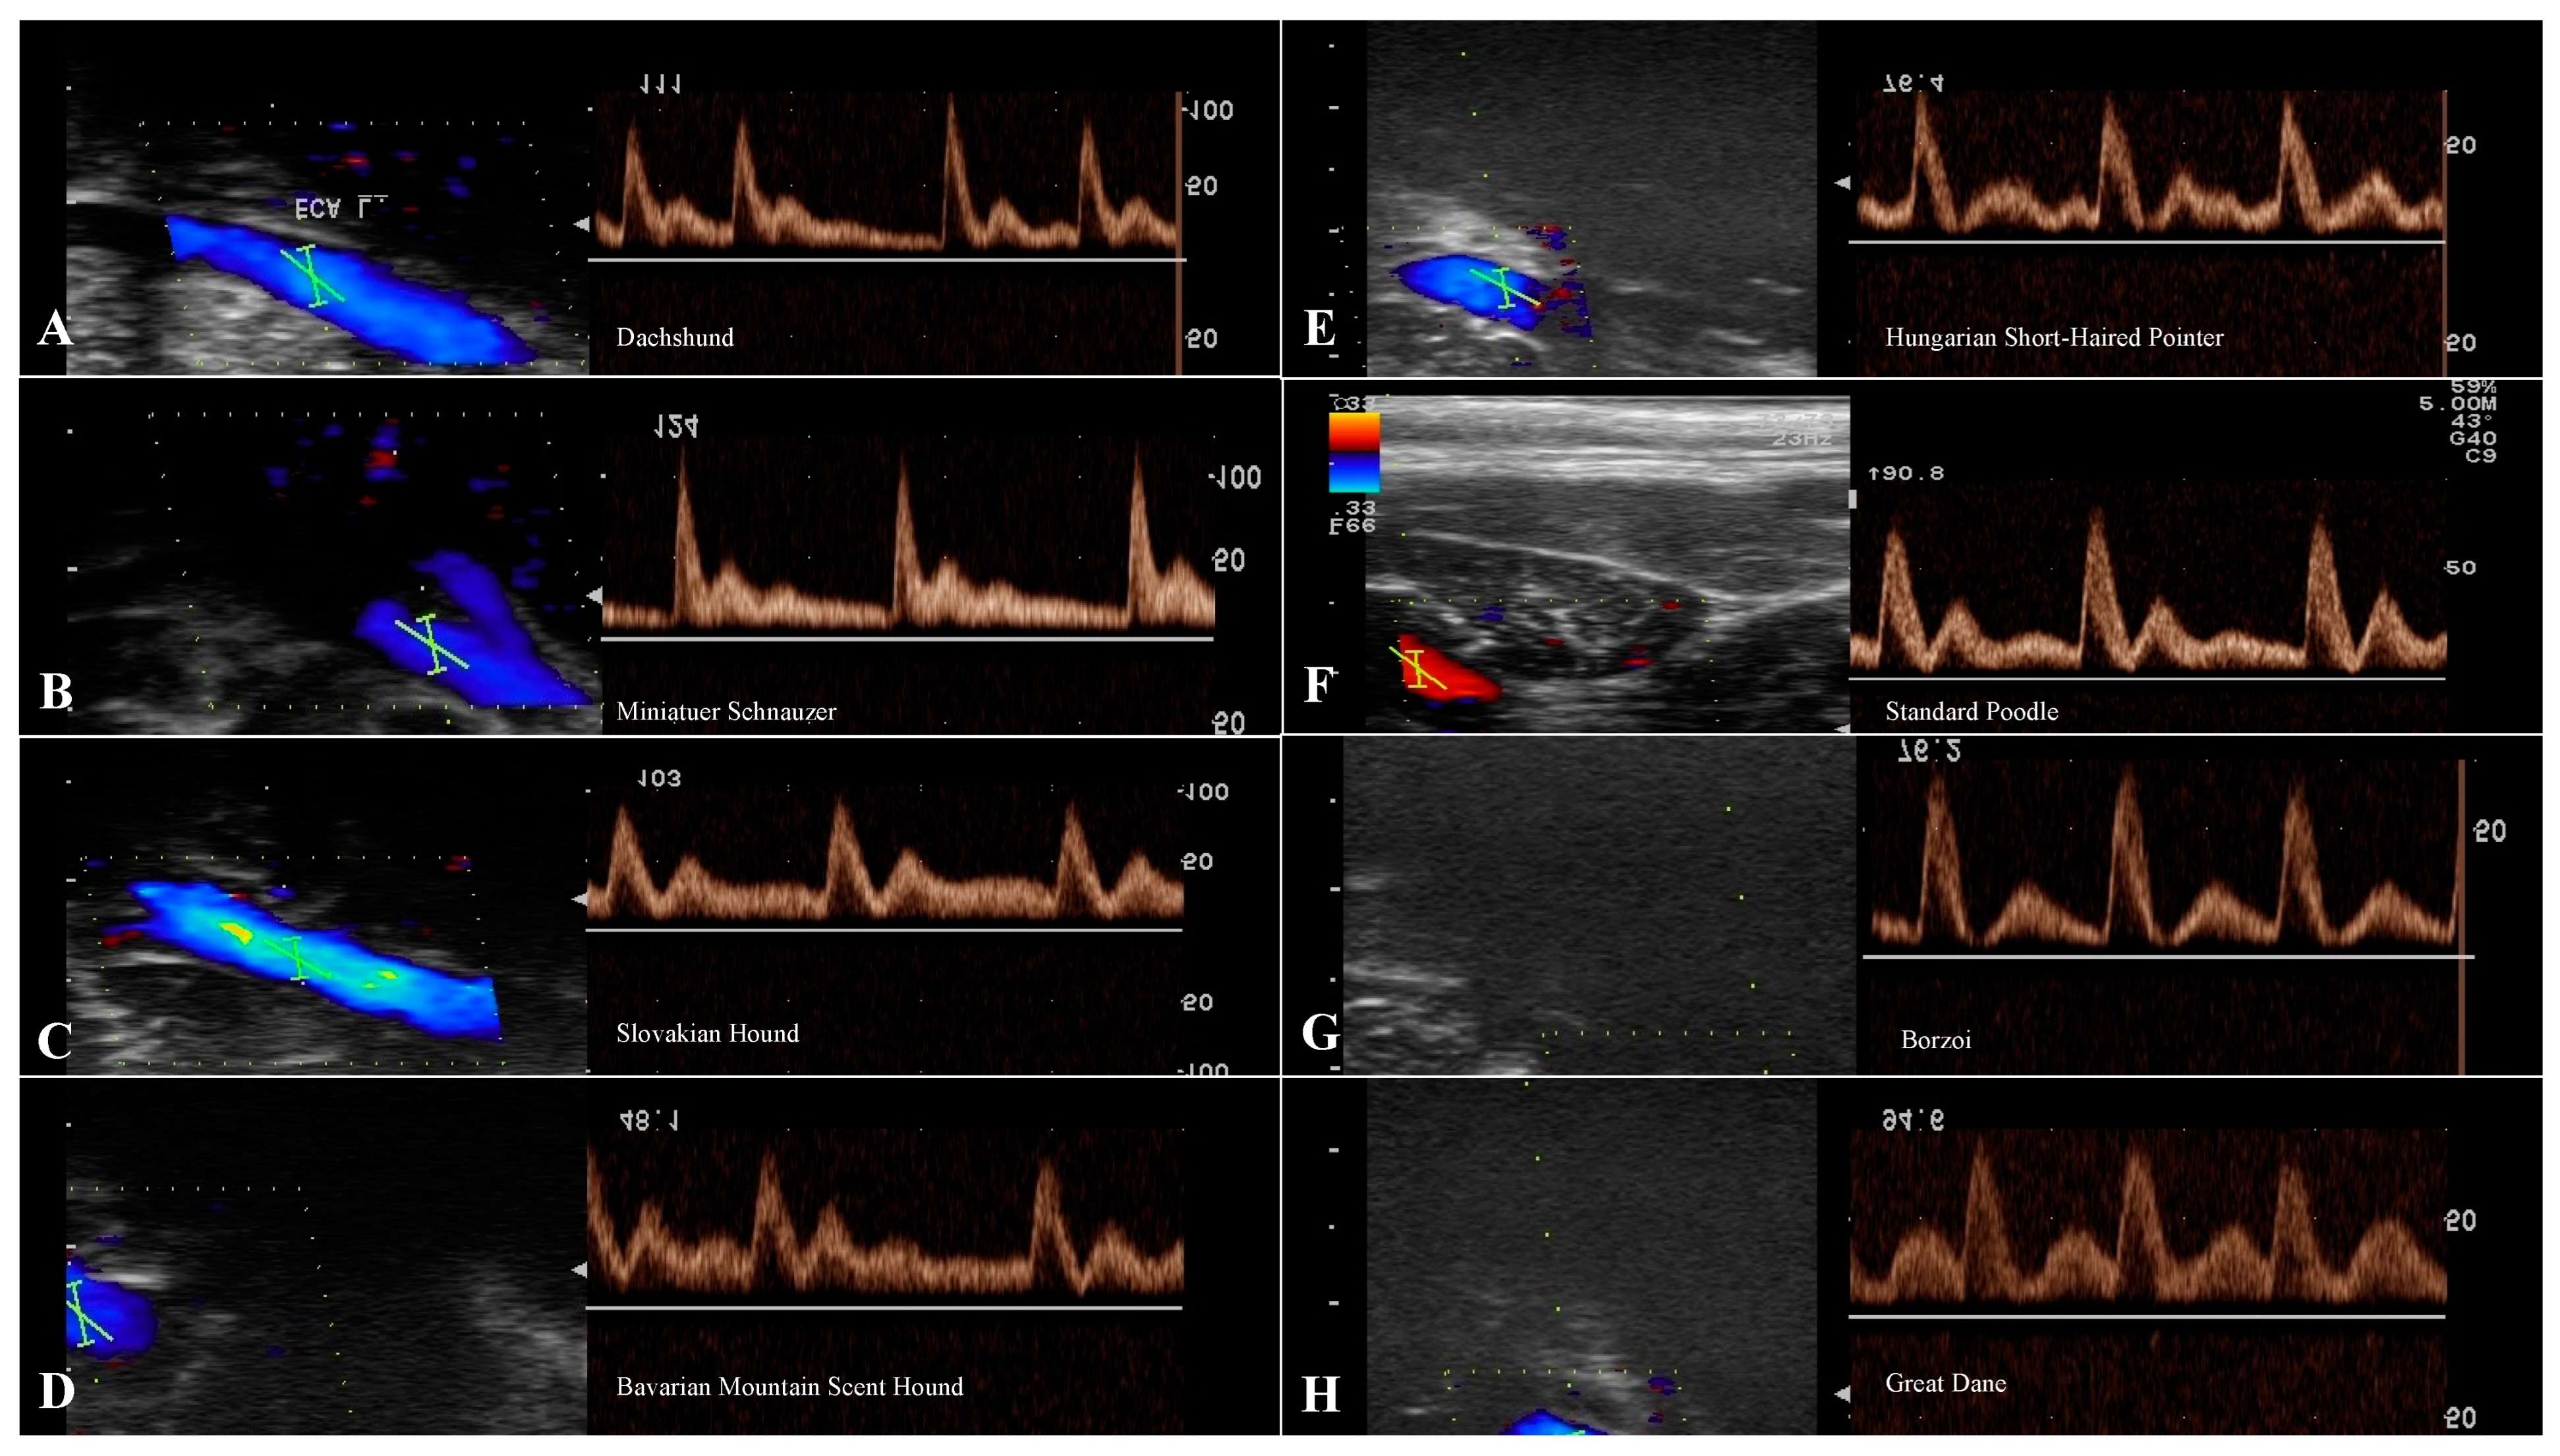

3.4. Evaluation of the ECA

| ECA | ||||||

|---|---|---|---|---|---|---|

| n | RI | PSV (cm/s) | EDV (cm/s) | S/D | ||

| Small breeds | Dachshund | 13 | 0.79 | 76.21 ± 13.77 | 17.71 ± 4.91 | 4.77 ± 1.34 |

| Miniature Schnauzer | 13 | 0.79 | 78.81 ± 19.23 | 18.05 ± 6.02 | 4.76 ± 1.17 | |

| Medium breeds | Slovakian Hound | 13 | 0.74 | 73.08 ± 13.76 | 19.78 ± 5.29 | 3.89 ± 0.92 |

| Bavarian Mountain Scent Hound | 13 | 0.71 | 80.45 ± 17.78 | 24.21 ± 7.91 | 3.57 ± 0.87 | |

| Large breeds | Hungarian Short-Haired Pointer | 13 | 0.73 | 71.74 ± 15.42 | 19.14 ± 2.58 | 3.86 ± 0.79 |

| Standard Poodle | 13 | 0.73 | 65.98 ± 15.01 | 20.42 ± 5.62 | 3.34 ± 0.54 | |

| Giant breeds | Borzoi | 13 | 0.79 | 76.13 ± 4.53 | 17.14 ± 1.23 | 4.55 ± 0.39 |

| Great Dane | 13 | 0.65 | 68.19 ± 10.15 | 22.6 ± 5.09 | 3.12 ± 0.59 | |